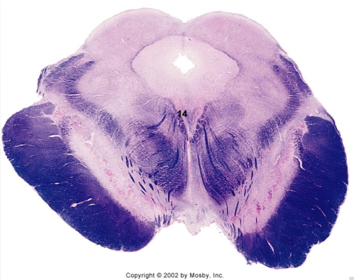

| Decussation of superior cerebellar peduncle | |

| Pontine nuclei | |

| Cerebral peduncles | |

| Central tegmental tract | |

| Medial lemniscus | |

| ALS | |

| Ventral trigeminothalamic tract | |

| MLF | |

| Mesencephalic V tract and nucleus | |

| Cerebral aquaduct | |

| Periaquaductal gray | |

| Superior colliculus | |

| Brachium of the inferior colliculus | |

| Decussated superior cerebellar fibers | |

| Red nucleus | |

| Substantia nigra | |

| CN III nucleus | |

| CN III rootlets | |

| Edinger-Westphal nucleus | |